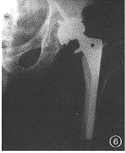

例7男,62岁,左侧全髋关节置换术后4年。由坐位起立时突然出现左侧髋关节剧烈疼痛,X线检查发现髋臼假体金属杯与聚乙烯内衬脱位。术中见髋关节周围有大量含有磨损金属颗粒的肉芽肿,髋臼聚乙烯内衬脱位并碎裂,髋臼金属假体与股骨假体直接接触,磨损颗粒引起髋臼与股骨近端骨溶解(图6)。

图1男,72岁,右全髋关节置换术后5年。右股骨假体内翻下沉,假体远端骨水泥断裂,髋臼假体周围有连续的透亮区图2女,65岁,人工股骨头置换术后5年。髋臼内壁磨损,容积性骨缺损图3女,68岁,右侧人工股骨头置换术。假体外翻位,假体柄自内侧骨皮质穿出图4男,40岁,股骨颈骨折后股骨头缺血性坏死。行人工股骨头置换术,人工股骨头过度前倾位置入图5男,67岁,左侧全髋关节置换术后7年。假体股骨柄断裂,股骨假体近端内翻,骨水泥周围透亮区形成图6男,62岁,左侧全髋关节置换术后4年。髋臼假体金属杯与聚乙烯内衬脱位,髋臼金属假体与股骨假体直接接触